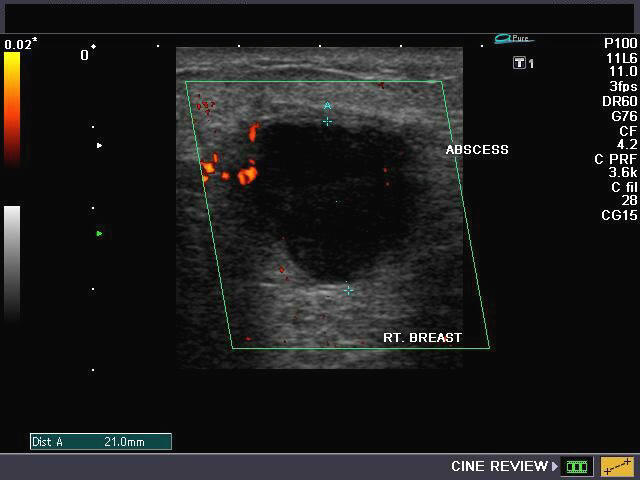

Abscesses in the breast are a common health problem. These are pockets of infection that may be treated with antibiotics, but they often require a surgical procedure. Abscesses can return repeatedly and they can be difficult to treat. In a new study in the Journal of the American College of Surgeons, researchers compared 68 patients with breast abscesses with another group of 68 without this problem. Those who smoked were more than six times more likely to have an abscess. In addition, smokers were more than 14 times more likely to have recurring abscesses. Patients with breast abscesses who smoke should strive to stop smoking, the researchers recommend, but research hasn't proven whether stopping will decrease the risk of the abscess recurring. I'm Dr. Cindy Haines of HealthDay TV, with the news that doctors are reading; health news that matters to you.